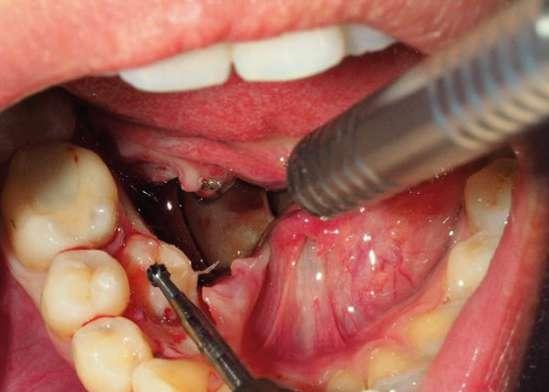

Una vez finalizada la intervención se procedió a realizar sutura interpapilar con sutura monofilamento 5/0 (Fig. 7 y 8).

Figuras 7 y 8. Zona quirúrgica suturada desde una visión oclusal y vestibular.